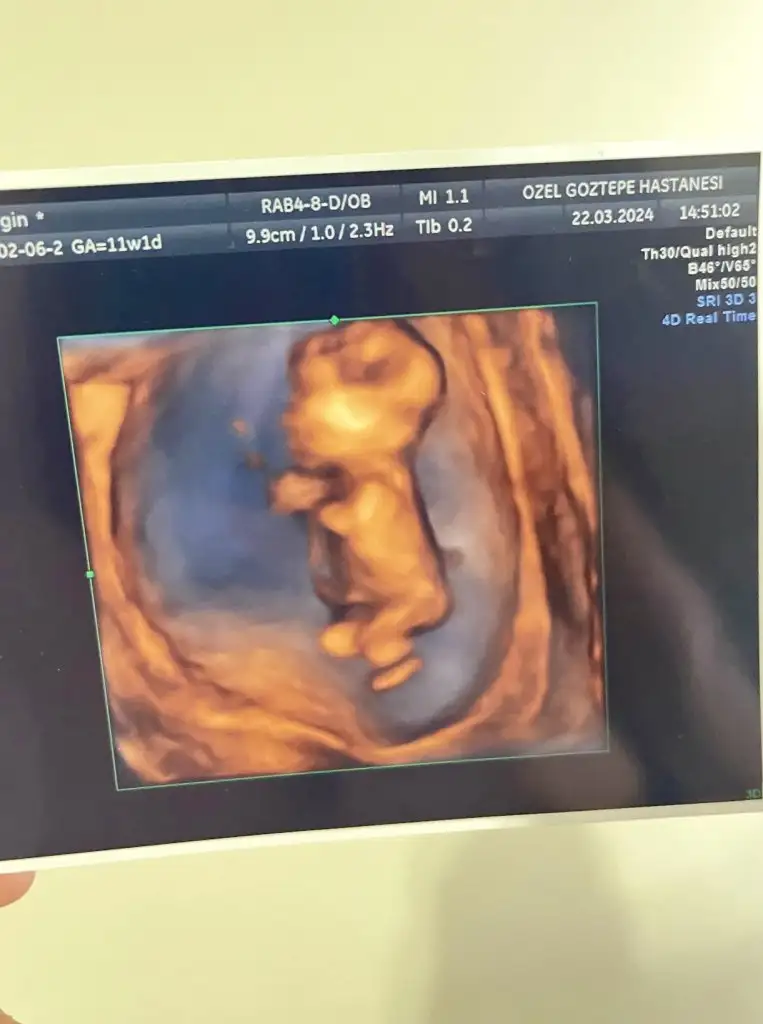

Erkek mi acaba bebişBenim tospiğime bi bakar mısınız kordonu bileğine mi dolamış o neCuma günüydü randevum yine cinsiyet tahmini alabilirim sizlerden

Totosu çok tatlı değil mi ayy ısırıcam nazar değmesin

Sizlerden de fotolar bekliyorum güzel anneler. Birbirimize nazarımız olmaz bence

Oooy maşallahh totişi ısırmak serbest mi annesiBenim tospiğime bi bakar mısınız kordonu bileğine mi dolamış o neCuma günüydü randevum yine cinsiyet tahmini alabilirim sizlerden

Bence kesinlikle erkekBenim tospiğime bi bakar mısınız kordonu bileğine mi dolamış o neCuma günüydü randevum yine cinsiyet tahmini alabilirim sizlerden